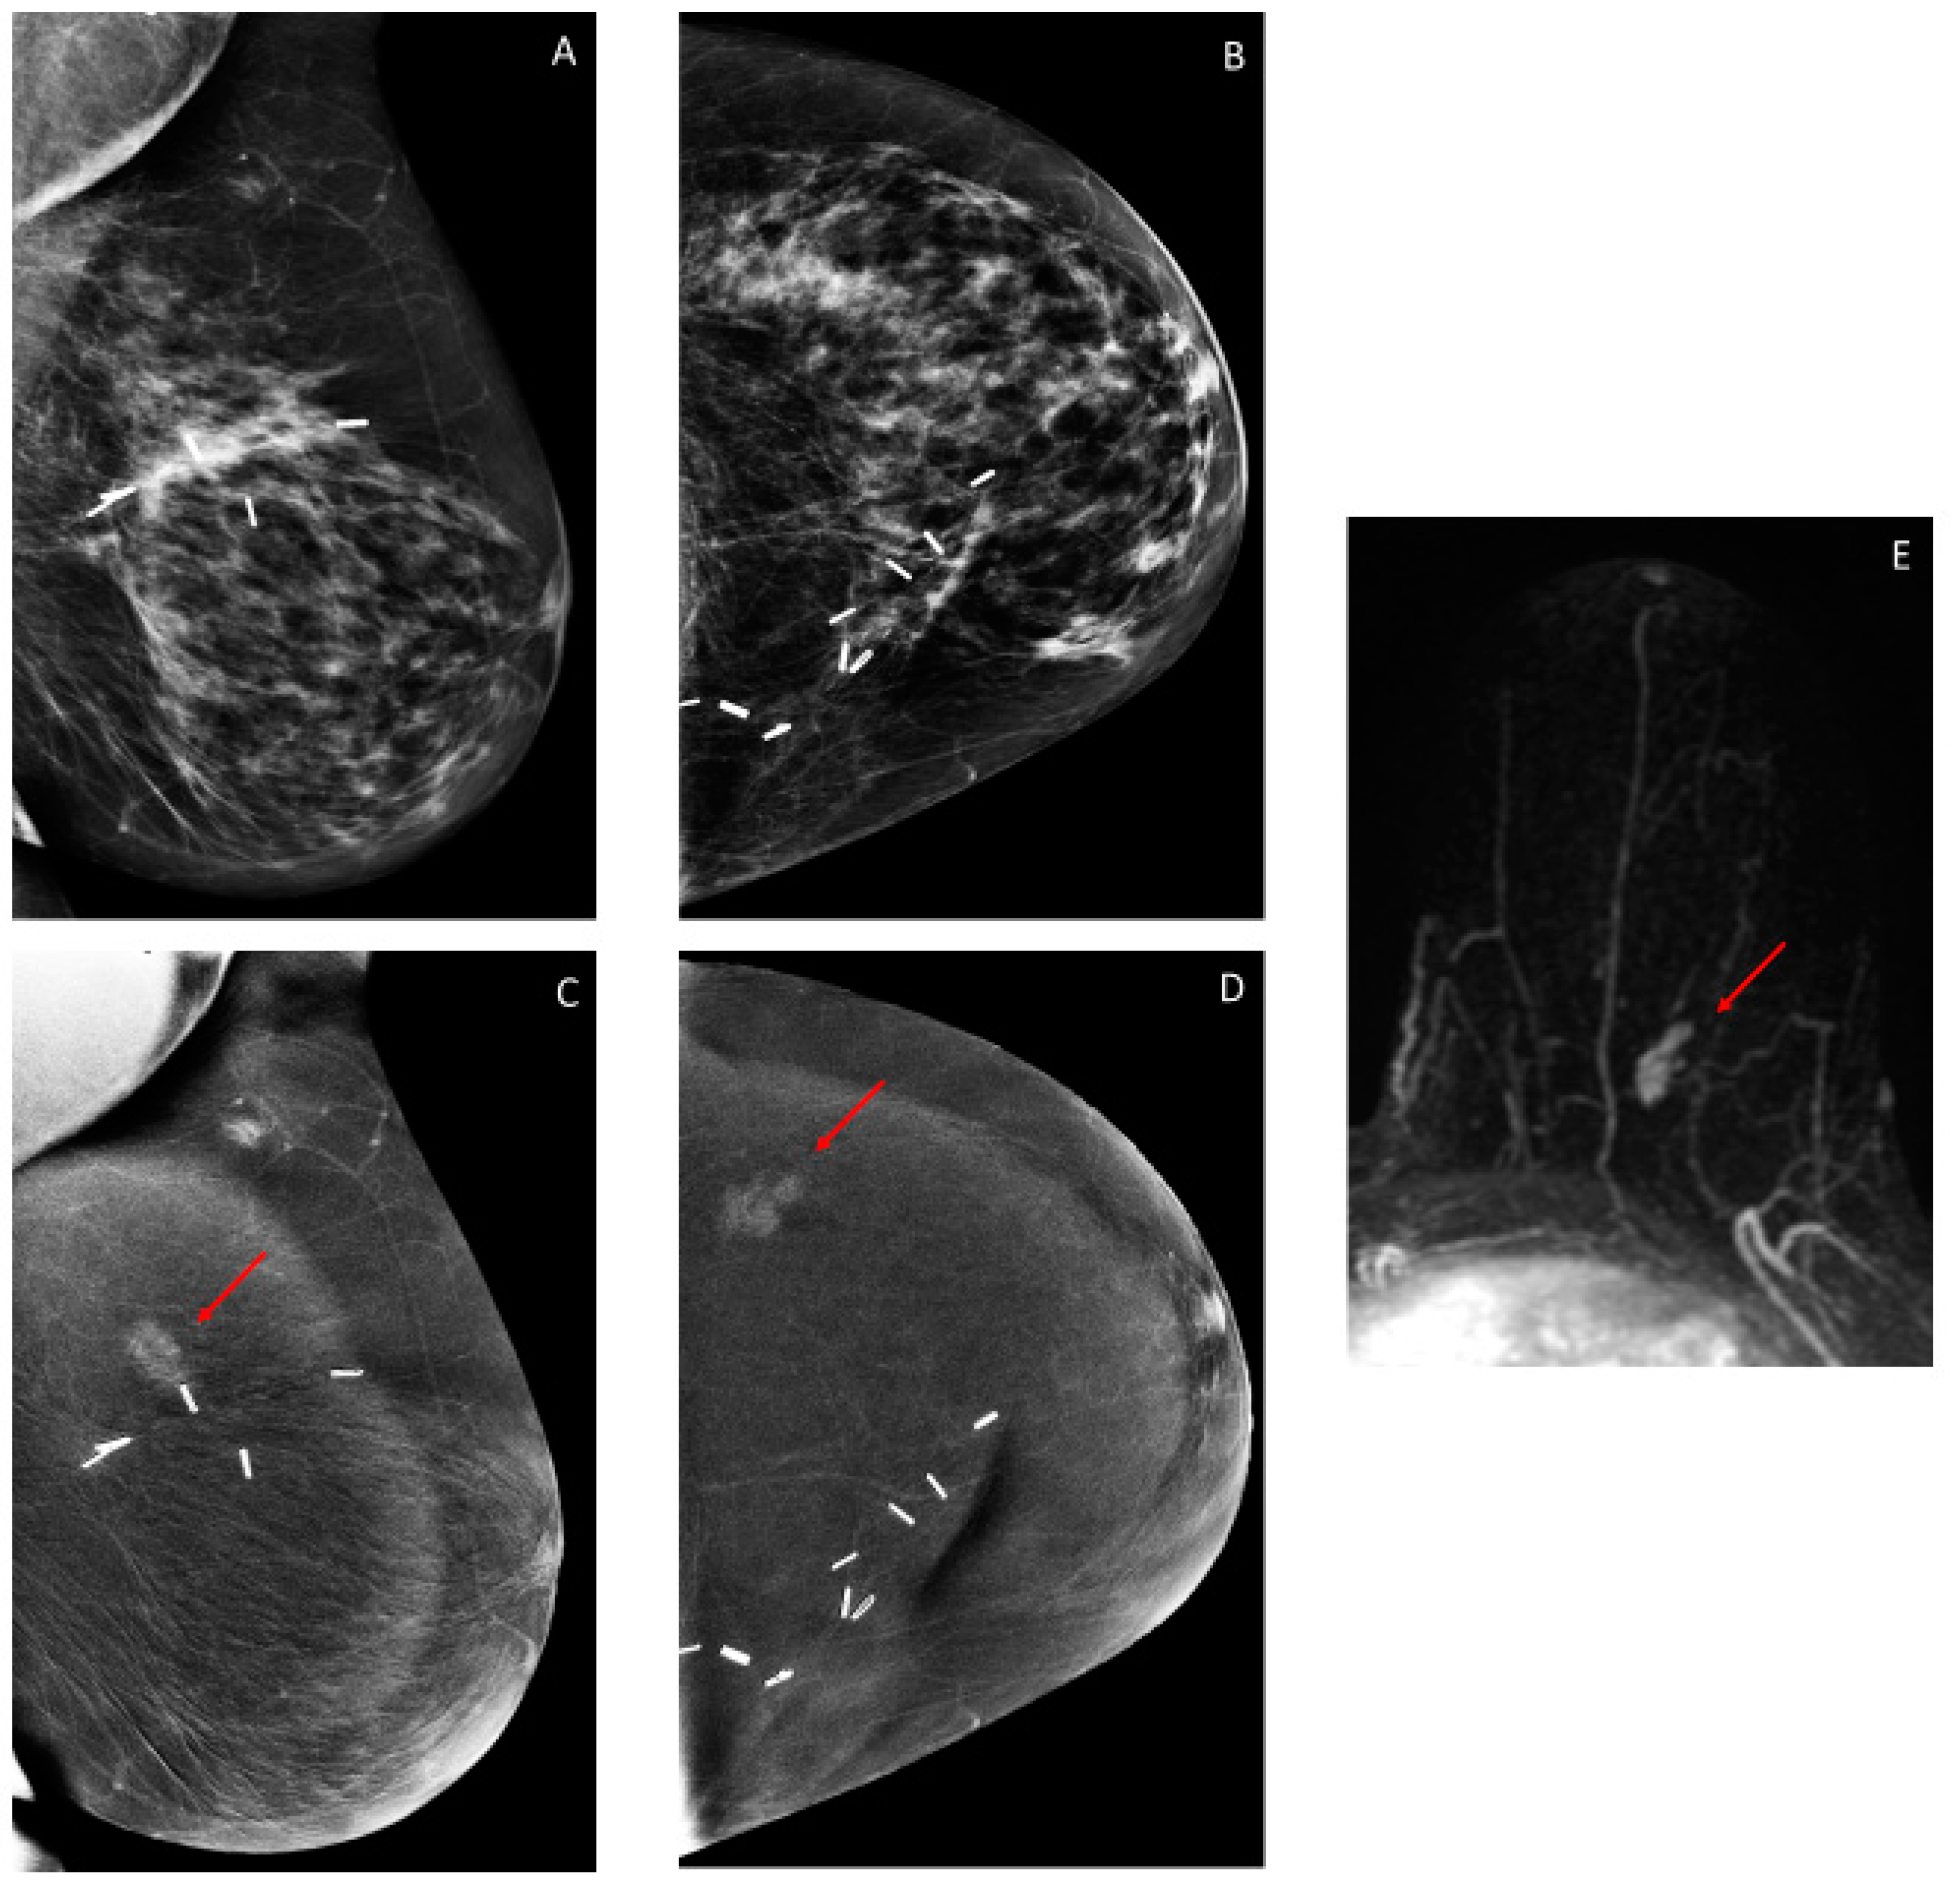

3.2. Findings on Low-Energy Images, With or Without Enhancement

3.3. Additional Findings on Iodine Images

3.4. Overall CEM Results